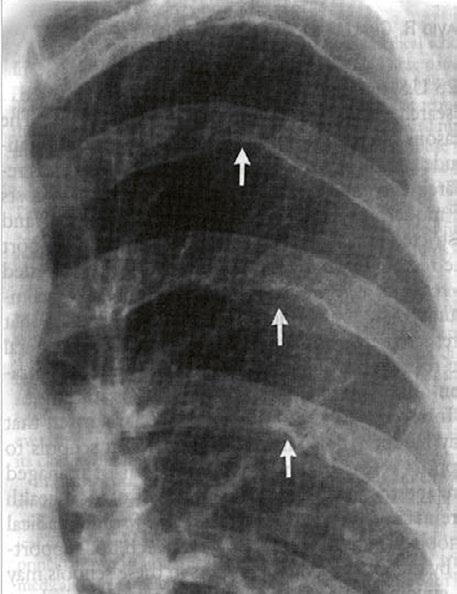

Supravalvární pulmonální stenóza a stenózy větví plicnice bývají součástí komplexních VSV (např. Fallotovy tetralogie) nebo syndromů (Williamsův syndrom, syndrom Noonanové, syndrom vrozené rubeoly, Alagillův syndrom aj.) (Obr. 45.39). Získané stenózy větví plicnice, ale i úplný uzávěr větve plicnice můžeme vidět po spojkových operacích podle BlalockaTaussigové (Obr. 45.40, Obr. 45.41). Pro zobrazení supravalvárních a periferních stenóz plicnice je optimální CT angiografie (Obr. 45.40, Obr. 45.41, Obr. 45.42, Obr. 45.43).

Obr. 45.40 CT angiografie, 8mm stenóza a deformace levé větve plicnice (šipka) po spojkové operaci podle BlalockaTaussigové v dětství LPA – levá větev plicnice, PA – kmen plicnice, RPA – pravá větev plicnice

Obr. 45.41 Uzávěr levé větve plicnice jako následek provedené spojky podle BlalockaTaussigové v dětství, CT angiografie